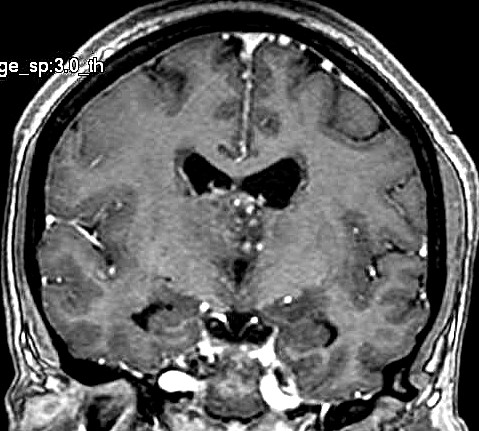

| Fem. 17a. |

| Nódulo sólido homogêneo preenchendo o III ventrículo, com limites precisos, com hipossinal em T1 e hipersinal em T2 e FLAIR, que se impregna por contraste paramagnético. Lesão menor implantada no assoalho do IV ventrículo provavelmente representa disseminação por via liquórica. |

| F. 17a. Tumor teratóide rabdóide atípico de III ventrículo. RM | HE | VIM, GFAP | HHF35, desmina, 1A4 | AE1AE3, EMA |